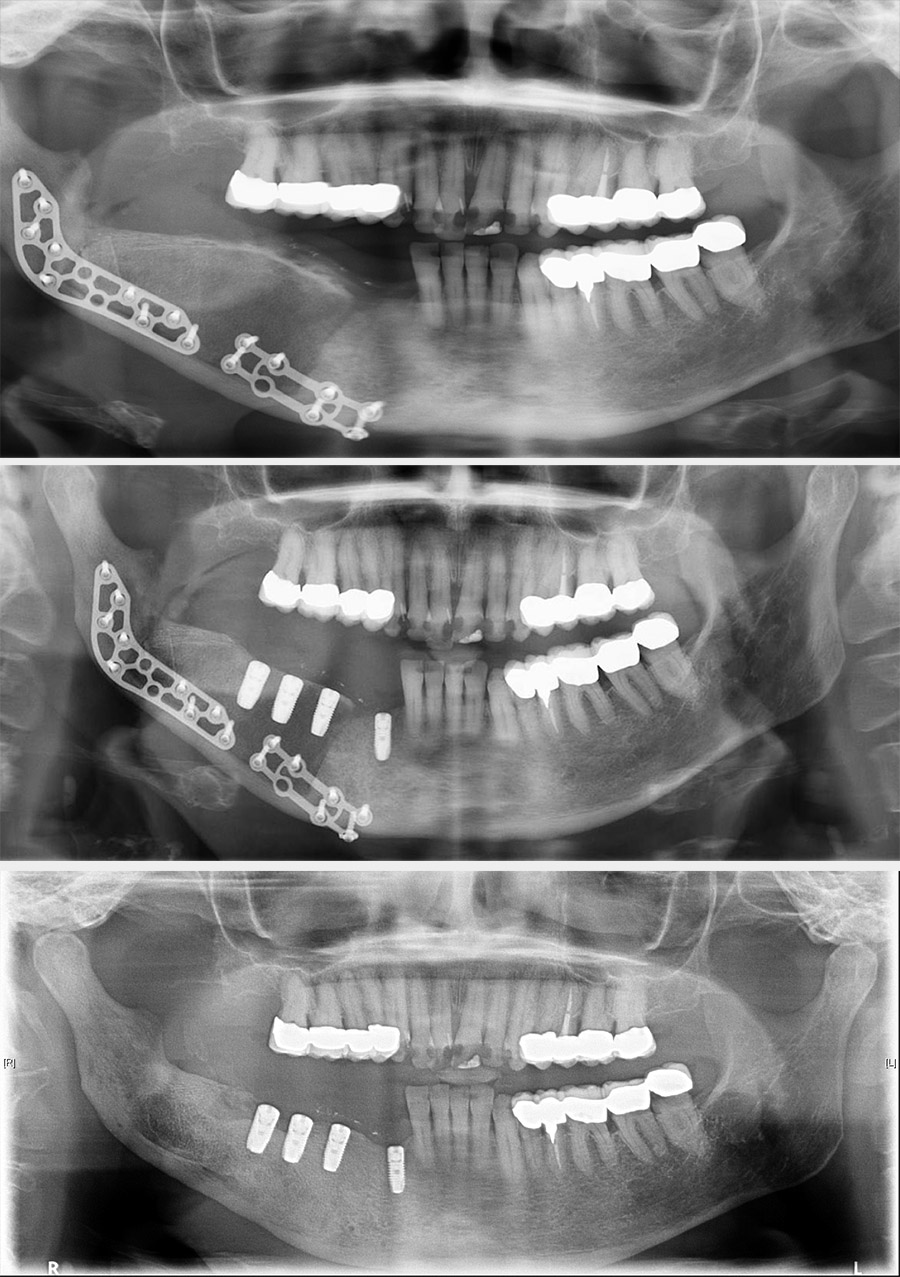

Treatment can be problematic. Long-term antibacterial therapy has been reported as being of benefit if given early in the course of the disease, but there are also reports that high-dose long-term antibacterial therapy has no beneficial effects. In more refractory cases, a course of corticosteroids and decortication may be of benefit. Hyperbaric oxygen therapy can be used to supplement the surgery although the evidence base is conflicting. Bisphosphonates have been advocated for chronic pain but have obvious conflicting risks regarding development of osteonecrosis. In some cases, more radical surgical intervention is required, such as resection of the affected region of the mandible (Figure 1 and Figure 2; note that the surgical techniques are essentially the same for some benign and malignant (see below) conditions).

Figure 1: Rim resection of sclerotic mandibular bone with dissection and preservation of the inferior alveolar and mental nerve (top); bone graft and reconstruction plates in place (bottom).

Figure 2: Postoperative condition. Top: X-ray image 6 weeks postoperatively; middle: X-ray image 4 months postoperatively, bone graft shaped and implants placed for dental rehabilitation; bottom: X-ray image 18 months postoperatively, reconstruction plates removed, implants integrated and ready to be loaded.